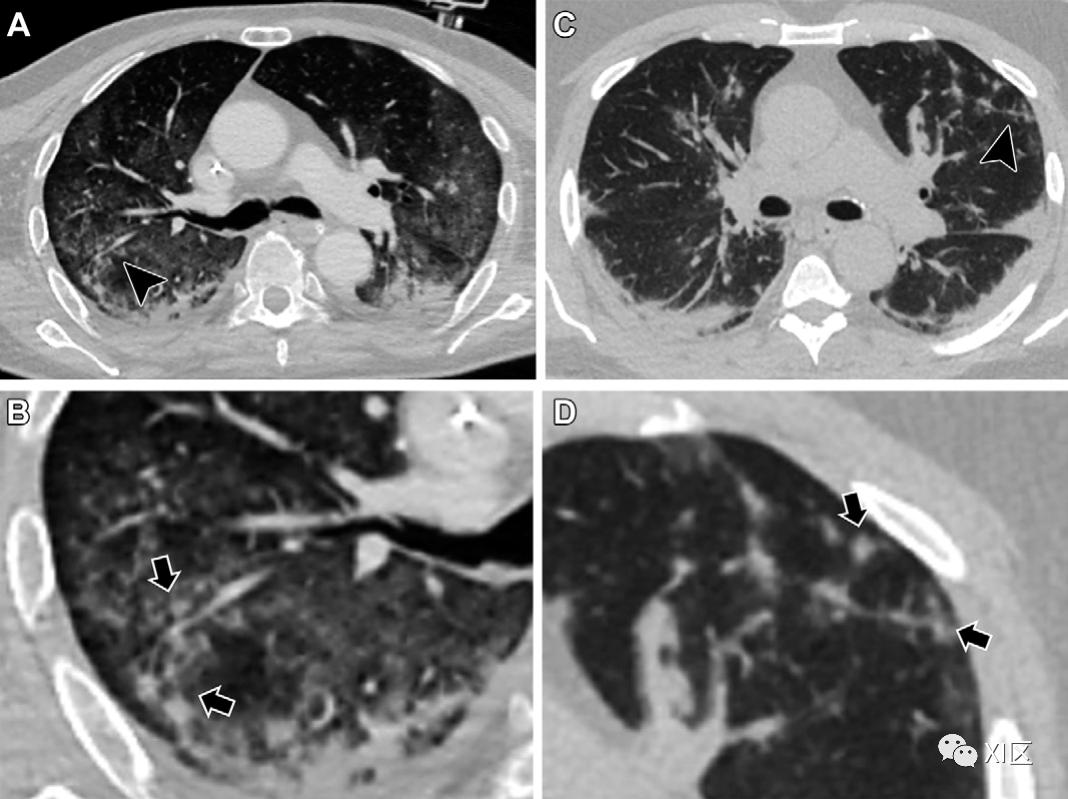

图3:一例53岁男性早期轻度新冠肺炎偶然组织病理学发现的代表性病例。该患者因肺腺癌接受了右上叶切除术和纵隔淋巴结清扫术。术后一周,患者出现高烧和咽喉痛,经实时PCR检测证实患有COVID-19。提取的右上叶标本经苏木精和伊红染色后显示出潜在的早期新冠肺炎组织病理学发现:肺泡壁局部扩张伴炎性细胞浸润(黑色箭头),II型肺细胞增生(白色箭头),以及空腔中的一些肺泡巨噬细胞(箭头)(标尺:100μm)。患者病情好转,出院后无临床或放射学恶化。根据这些组织病理学发现,与机化性肺炎相一致的CT模式是轻度新冠肺炎患者的主要特征(图4)。事实上,高达50%-70%的轻度新冠肺炎患者经常报告有外周或支气管血管周围分布的GGO和小面积的实变,代表了CT上的机化性肺炎模式。当然,肺实质纤维化可能表现为机化性肺炎的CT表现之一,如小叶周围增厚、牵引性支气管扩张或局灶性体积减少。其他报道的轻度新冠肺炎患者的CT特征包括GGO伴间质增厚(即疯狂铺路征外观)、小叶周围GGO和反晕征。轻度新冠肺炎的这些CT特征相对难以与隐源性机化肺炎或继发性机化性肺炎模式与其他原因区分开来,例如流感肺炎,提醒我们机化肺炎模式并非新冠肺炎特有,而是对肺损伤的一般反应。

图4:与机化性肺炎相似的轻度和缓解性新冠肺炎的典型CT图像。(A–C)一名患有轻度和可逆性新冠肺炎的65岁男性患者的轴位CT平扫图像显示,周围和小叶周围分布着GGO(虚线轮廓)和反晕征(箭头),以及血管充血(箭头)。中重度进展期新冠肺炎的放射学-病理学相关性